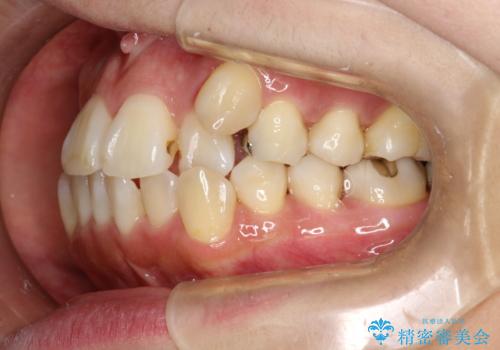

- これから矯正治療を始めるため、今の状態でも歯をきれいにしておきたいとのことでした。PMTC60分コースを行いました。

プラーク(細菌の塊)や歯石がたまると歯の表面はザラつきいてきます。そのザラつきは歯周病や虫歯菌の棲家となります。そのまま放置すると、歯肉が腫れてきたり、歯肉から出血したり、口臭が強くでたりします。とくに歯肉の境目は、歯磨きで汚れを除去することが難しく、プラーク(細菌の塊)や歯石が溜まりやすい場所です。

歯並が、がたついている場合はなおさら汚れが溜まりやすいです。矯正治療前や矯正中、定期的にPMTCをすることで、矯正治療中の歯肉トラブルを防ぐことにつながります。